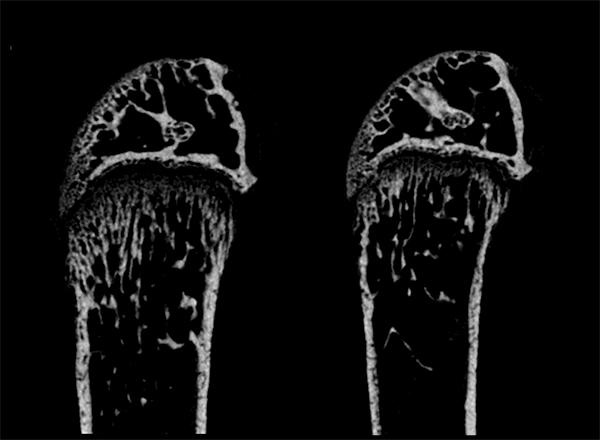

image: A computed tomography image shows more bone breakdown in the femur of a mouse with Fbw7 gene knocked out similar to people with Hadju-Cheney syndrome (right) compared to control mice (left). view more

・NOTCH2 の分解を抑制するマウスを作製して解析を行ったところ、 Hajdu-Cheney 症候群を模倣した骨粗鬆症様の表現型が観察されました。さらに、本マウスに NOTCH2 の働きを阻害する薬剤を投与したところ、マウス骨密度の回復が認められました。